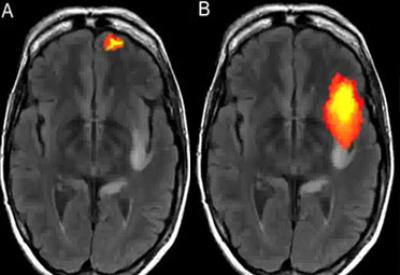

Sol tarafta dindar, köktendinci olan insanlardaki VMAT2 (Tanrı Geni) görülüyor. Sağda ise çok dindar olmayanların gen grafiği görülüyor.”